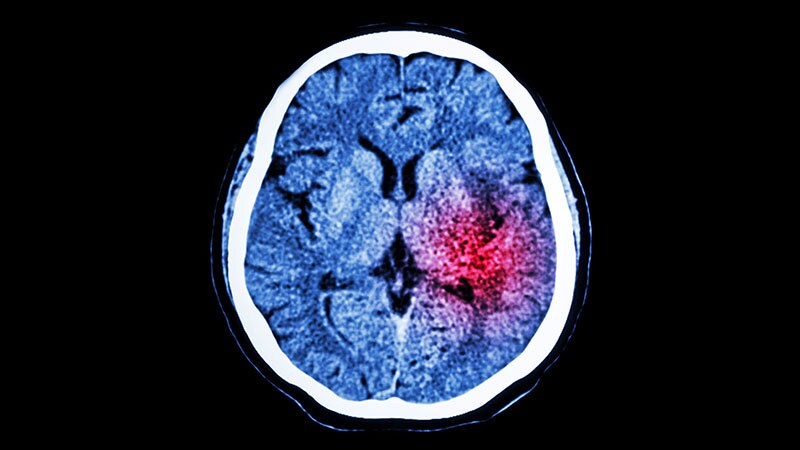

Taking ICH Cases Straight to Endovascular Center May Cause HarmRACECAT trial results suggest the longer travel times to the comprehensive stroke center -- rather than going to a closer

primary stroke center -- could be harmful for patients having a hemorrhagic stroke.